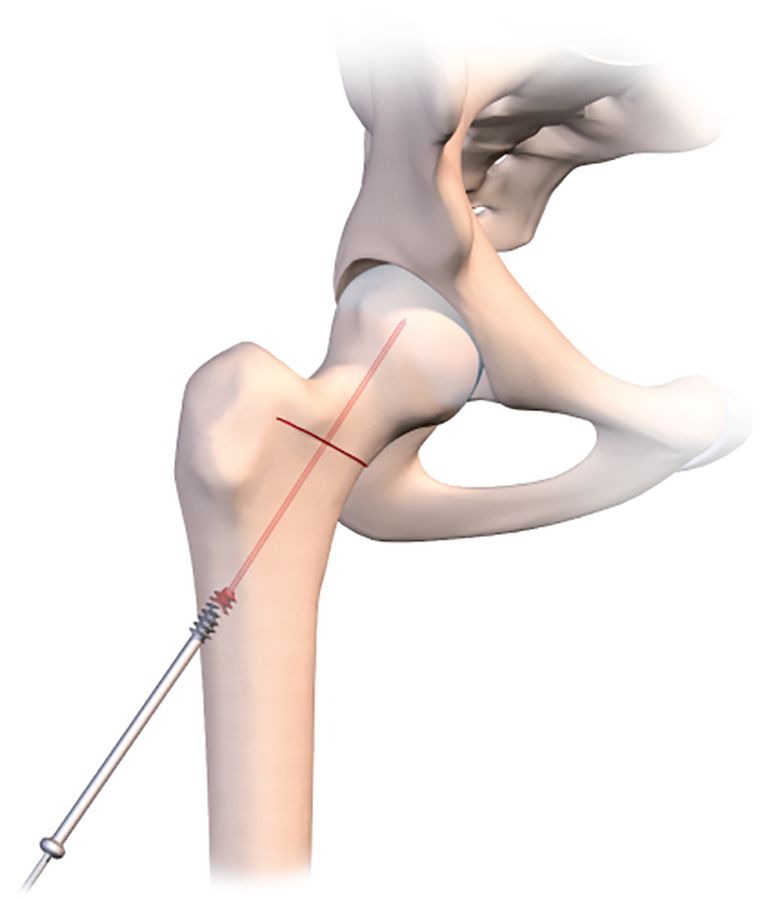

This osteotomy is easy to repair, using the same technique as for a normal badly impacted fracture of the base of the neck of femur, with two or three large diameter cannulated screws.

Just before using the orthopaedic table to begin the compression, it is a good idea to use a tibial drill guide (as for cruciate ligament repair) (Figs. 2b, c, d).

This makes it much easier to guide a pin into the osteotomy line that has just been created. The pin should of course sit just within the osteotomy line, without going any further. Applying compression will close the line and fix the pin in the neck and head of femur. With the osteotomy line closed and the pin in place, the final stage is to insert a 7mm cannulated screw to stabilize the fixation. A second or even third screw may be used if necessary. The image intensifier should be used to check the correct placement of the screws (Fig. 2e).